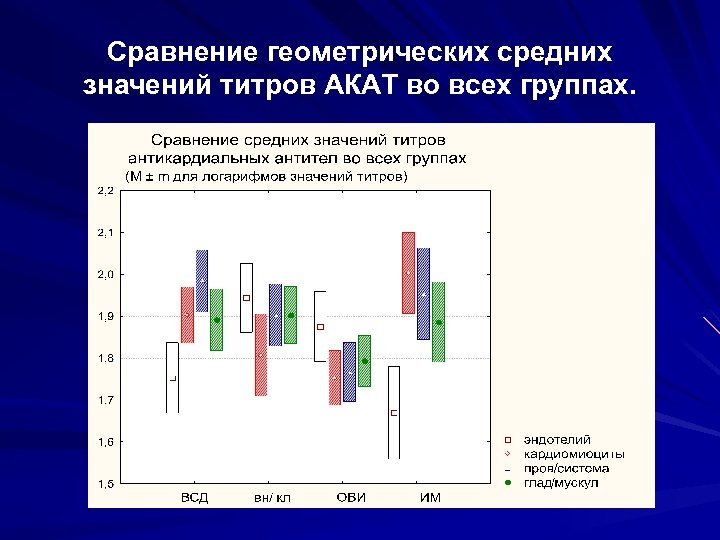

Сравнение геометрических средних значений титров АКАТ во всех группах.